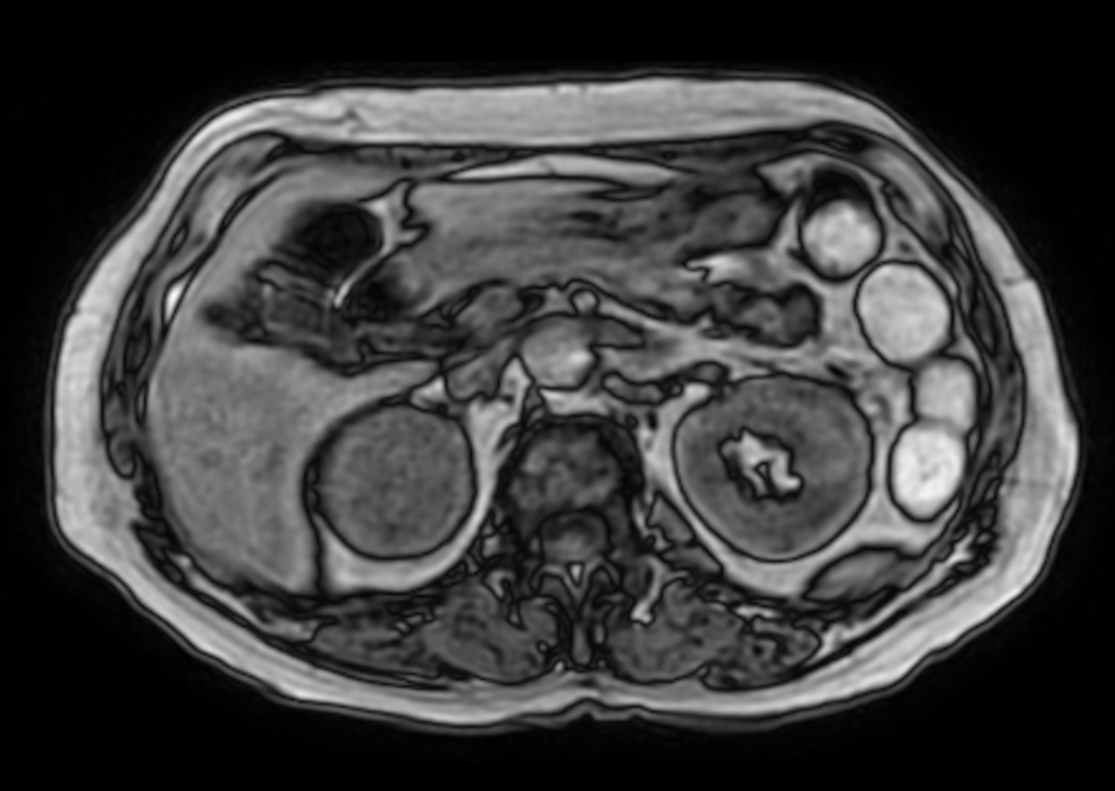

Patient with a kidney lesion. The ExamCard includes techniques for 3D imaging (PelvisVIEW, eTHRIVE) allowing for multiple image directions in one single scan, efficient fat-free imaging over large field-of-views (mDIXON XD), a multi-phase contrast-enhanced sequence (4D FreeBreathing) to improve imaging confidence and Compressed SENSE to accelerate the entire exam.

4D FreeBreathing

4D FreeBreathing (MIP)

4D FreeBreathing (subtraction)

T1w mDIXON XD FFE with gado (Water only)

T1w mDIXON XD FFE with gado (In Phase)

T1w mDIXON XD FFE with gado (Out Phase)